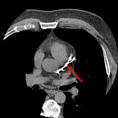

Cardiac CTA

A coronary blockage is seen at the arrow.

|

The same blockage can been seen in different angles.